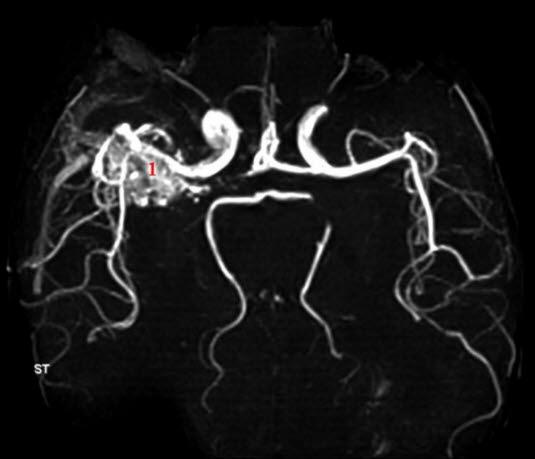

AV-malformasjon (MR angio)

MR angio uten kontrast viser blodårenøste (1)